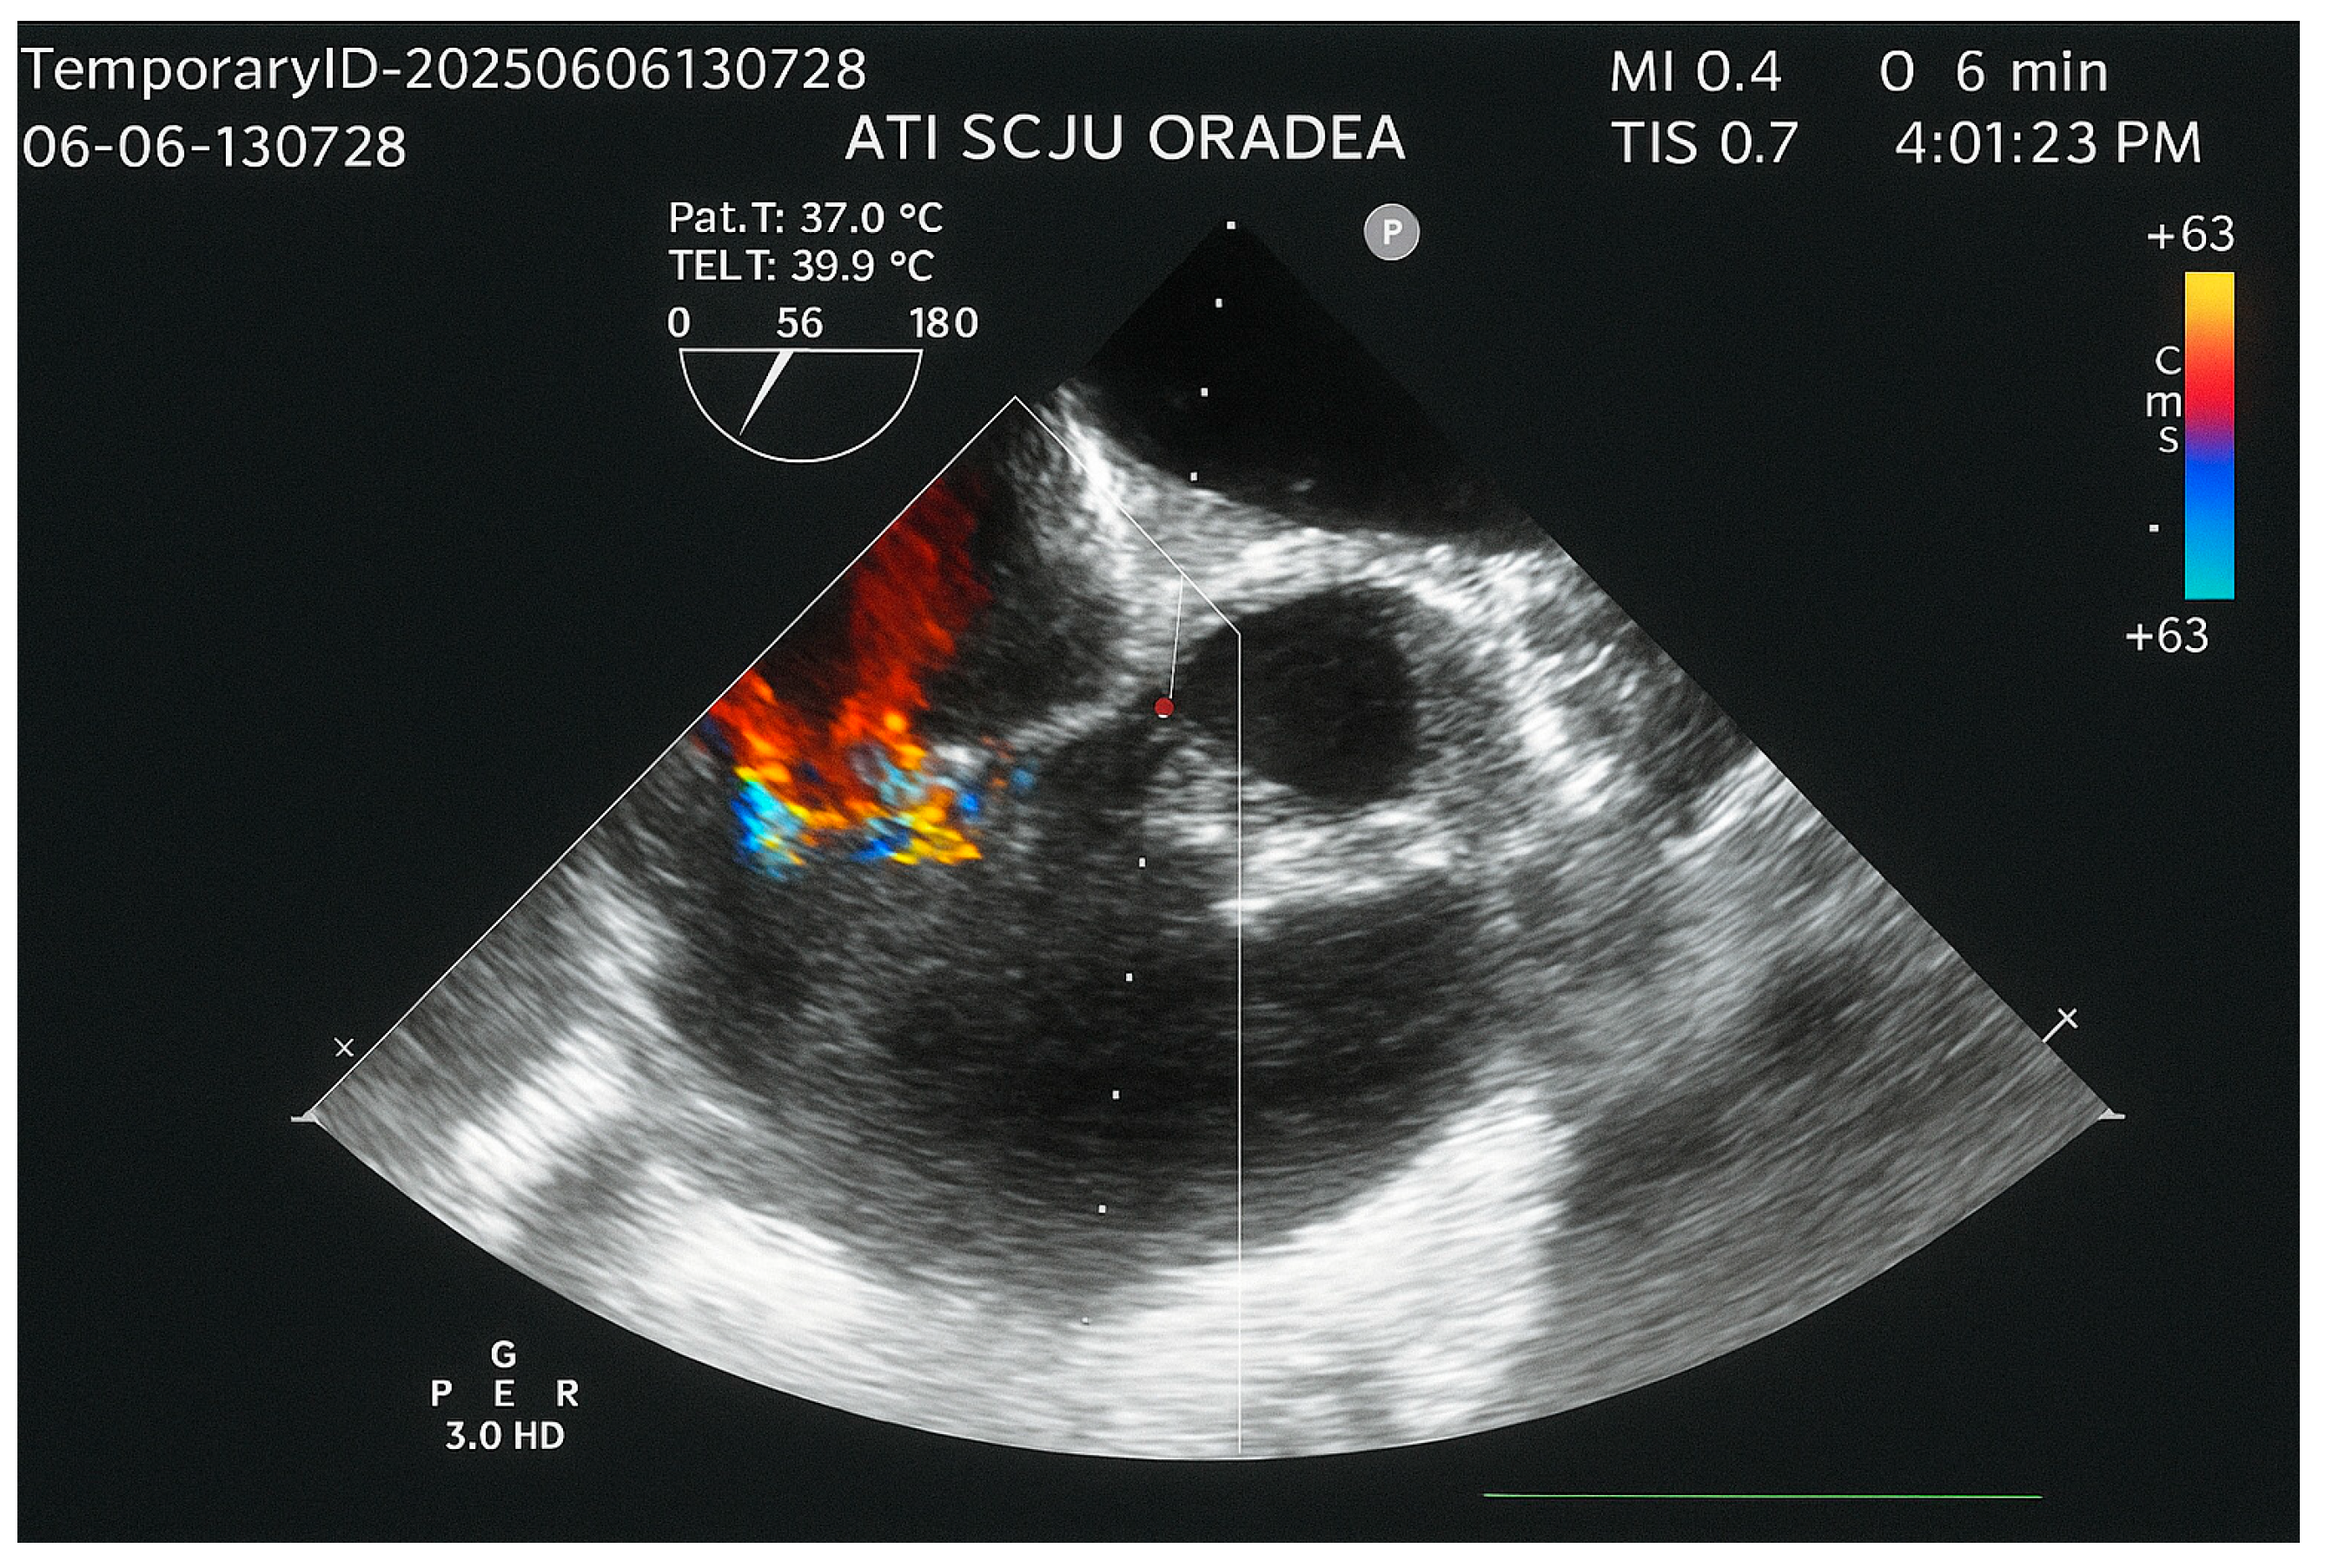

2. Case Report